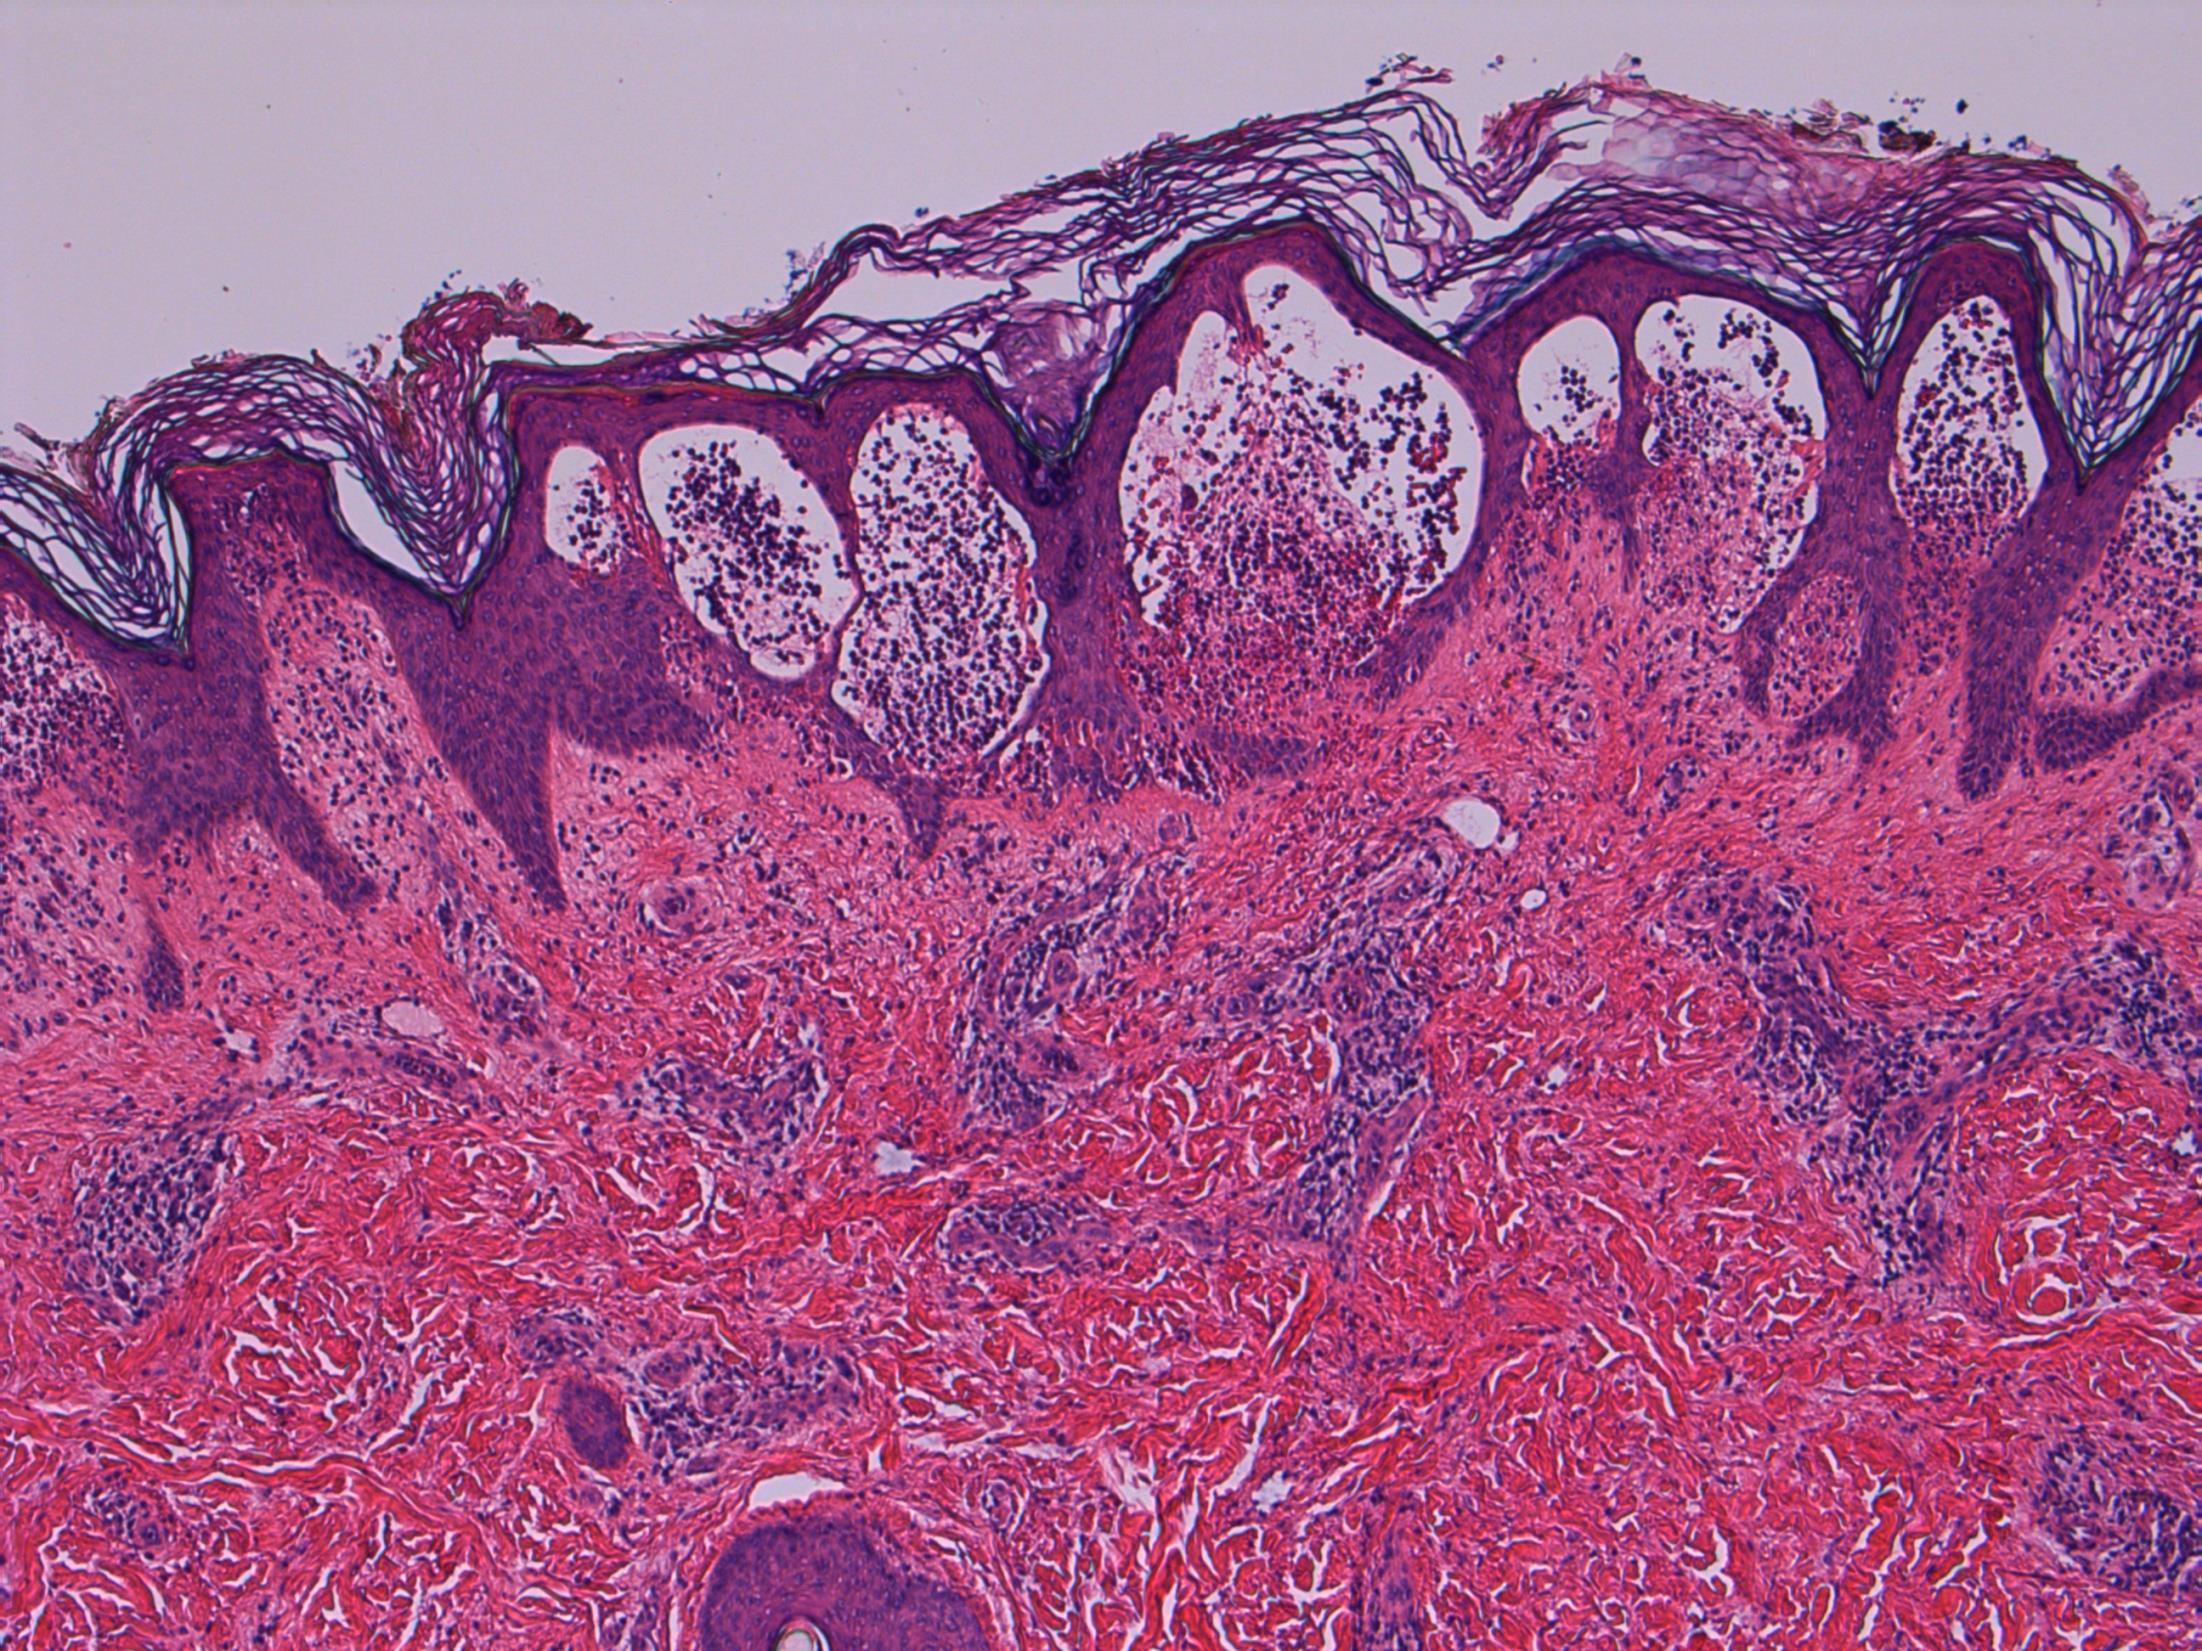

82M. Partial maxillectomy for a 3cm keratotic growth. Two previous biopsies were nonconclusive.

• Maxilla – Verrucous carcinoma

Verrucous carcinoma

Description: Abrupt transition between tumour and epithelium. Plump papillary invaginations of thickened and infolding epithelium, hyperkeratosis. Lack of cytological atypia, suprabasal mitoses. Retraction of normal epithelium at margin. Diagnosis: Verrucous carcinoma Differential Diagnosis:

Conventional SCC – cellular atypia • Squamous papilloma – more exophtyic & branching, less keratin • Reactive inflammatory epithelial hyperplasia – most difficult but rete pegs more slender and anastomosing; no mitoses; macro correlation Plan: Correlate with previous biopsies ( often quite bland so can be inconlusive) Examine further blocks for worse areas and measure margins. Comments: In head and neck – oral cavity and larynx Often large, locally aggressive, pushing margin Better prognosis than SCC

3.5 Clinical features 3.0 Potential differential diagnosis with justification (correlate history too) 2.5 Description with diagnosis 2.0 Differential diagnosis with mention of verrucous carcinoma 1.5 Uncertain, but some mention of ‘atypia’ 1.0 Benign diagnosis Case 19